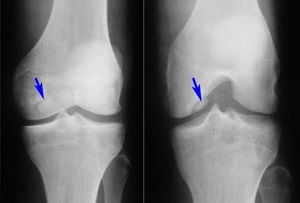

- Рентгенография поражённых суставов в двух проекциях (выявление остеопороза, наличие эрозий и узур, а также оценка степени сужения суставной щели);